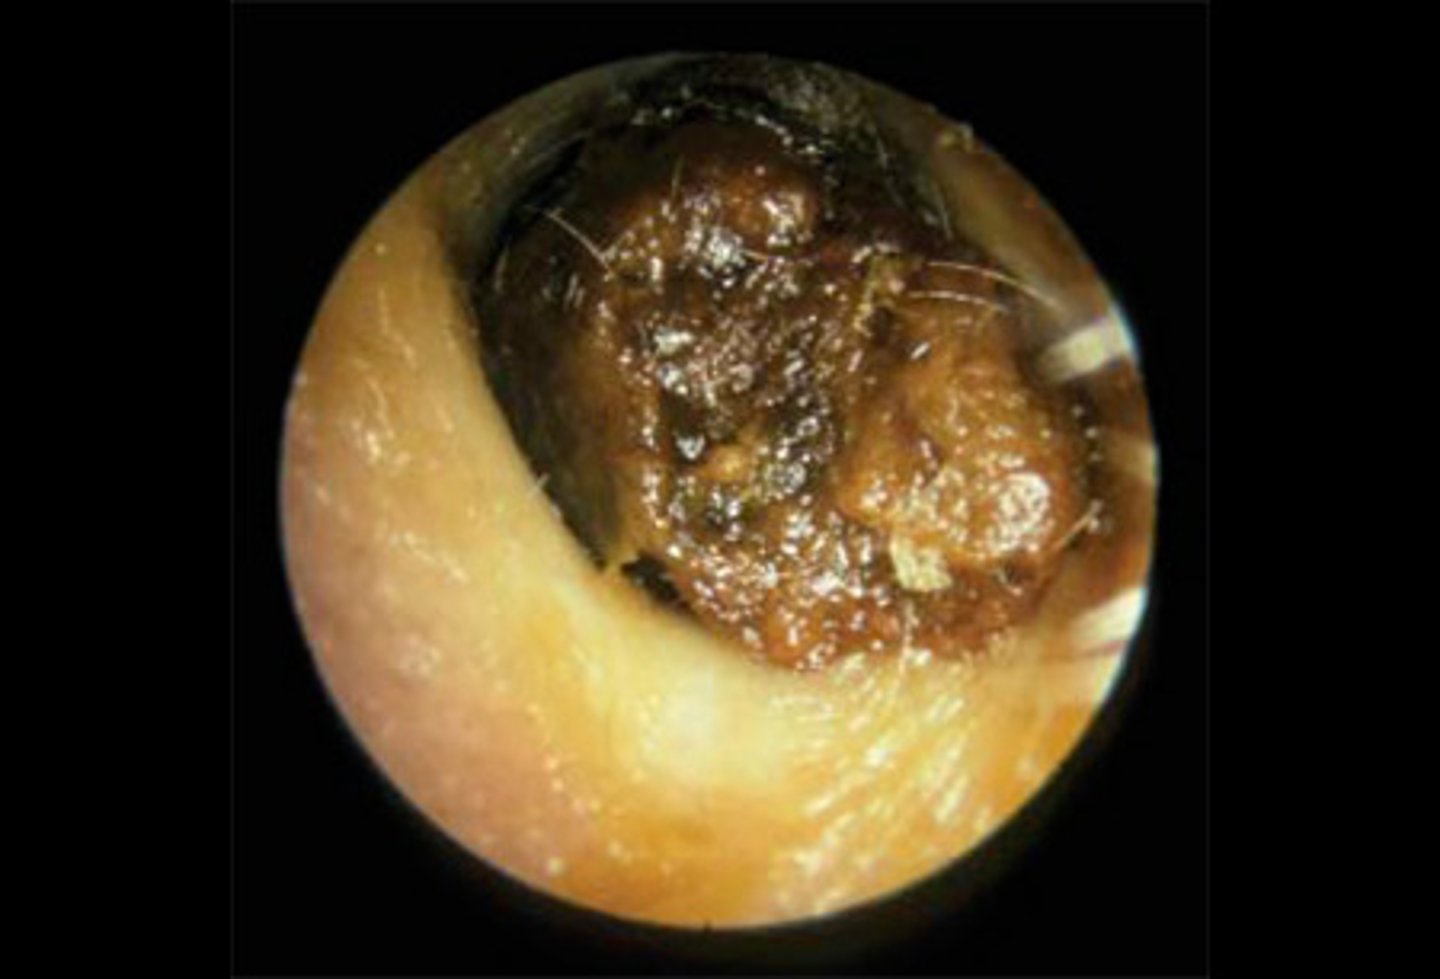

Cerumen impaction

plug of ear wax

<p>plug of ear wax</p>